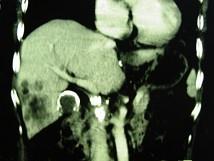

问题 女,66岁,右上腹痛,发热伴有黄疸两月余,消瘦、纳差,影像检查如图,最可能的诊断是()

选项 A.慢性胆囊炎及局灶性脂肪肝 B.胆囊壁钙化及肝血管瘤 C.胆囊癌肝转移 D.肝内胆管细胞癌 E.胆囊癌及原发性肝癌

答案 C